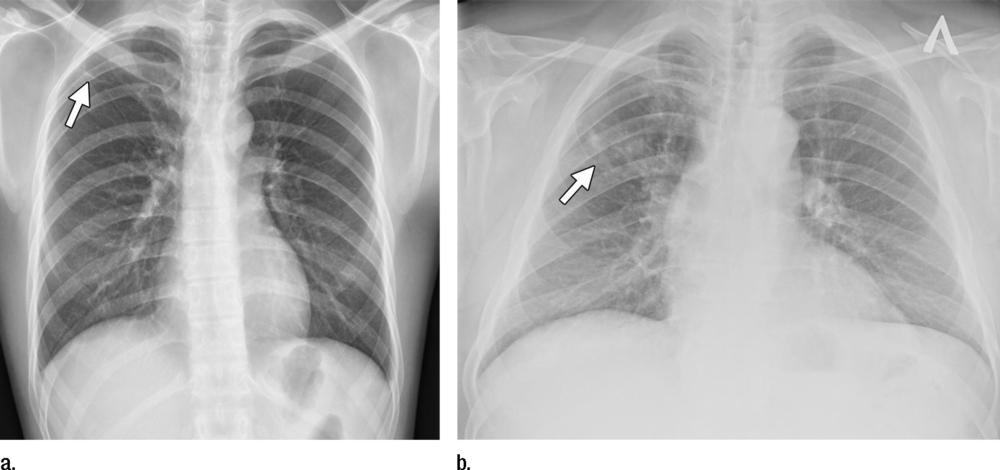

Figure 4 (a) Posteroanterior chest radiograph shows upper lobe opacities with pathologic analysis–proven active TB. (b) Same posteroanterior chest radiograph, with a heat map overlay of one of the strongest activations obtained from the fifth convolutional layer after it was passed through the GoogLeNet-TA classifier. The red and light blue regions in the upper lobes represent areas activated by the deep neural network. The dark purple background represents areas that are not activated. This shows that the network is focusing on parts of the image where the disease is present (both upper lobes).